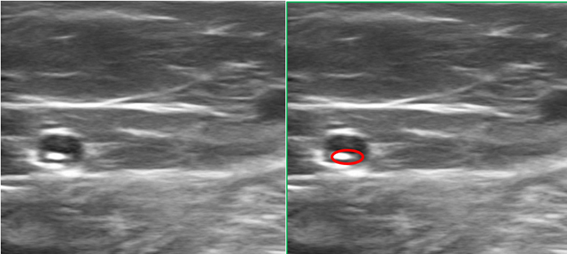

Figure 4 Image A: Foam administration with the catheter fully introduced. Image B: Partial removal of the catheter which allows progressive distribution along the vessel.

Administration is carried out under DUS, with slow administration of 2 cc of foam, and administration of another 2 cm of foam in withdrawal, observing the adequate distribution of the medication along the vein. Administration of the drug should be painless. In our case, Trendelenburg placement is performed prior to the administration of the foam, which increases the safety of the treatment while reducing the diameter of the vessel, facilitating contact with the endothelium of the Polidocanol foam, and improving its effectiveness.